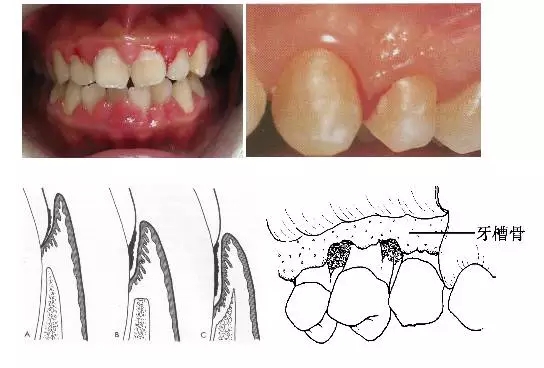

1、牙齦改變:正常牙齦粉紅色、菲薄而緊貼牙面,附著齦有點彩。患牙齦炎時游離齦和齦乳頭呈鮮紅或暗紅色,齦緣變厚,齦乳頭圓鈍,不再緊貼牙面;由于結締組織內炎性浸潤及膠原纖維消失,使原來致密堅韌的牙齦變得松軟脆弱,缺乏彈性;同時由于牙齦腫脹或增生,齦溝深度增加,但上皮附著水平仍位于正常的釉牙骨質界,即出現假牙周袋。

3、牙周袋形成:牙周袋是病理性加深的齦溝,是牙周炎最重要的病理改變之一。按照袋底的位置,可將牙周袋分為骨上袋和骨下袋;按牙周袋累及牙面的情況可將其分為單面袋、復合袋、復雜袋。

4、牙槽骨吸收:牙槽骨吸收是牙周炎的另一個主要病理變化,由于牙槽骨的吸收,使牙齒的支持組織喪失,牙齒逐漸松動,最終脫落或拔除。牙槽骨的吸收可分為水平吸收、垂直吸收、凹坑狀吸收等幾種類型。

5、牙齒松動和移位:由于牙周炎使牙槽骨吸收,牙周支持組織減少是牙齒松動的最主要原因;另外在咬頜創傷合并有牙周炎時,也可造成牙齒松動。由于患有牙周炎的牙齒缺乏牙周支持組織,所以,在咬頜創傷的不良咬頜力作用下,牙齒可出現病理性移位。